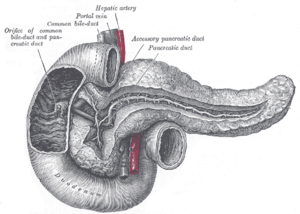

Bile produced by the liver is made up of water (97%), bile salts, mucus and pigments, 1% fats and inorganic salts.[24] Bilirubin is its major pigment. Bile acts partly as a surfactant which lowers the surface tension between either two liquids or a solid and a liquid and helps to emulsify the fats in the chyme. Food fat is dispersed by the action of bile into smaller units called micelles. The breaking down into micelles creates a much larger surface area for the pancreatic enzyme, lipase to work on. Lipase digests the triglycerides which are broken down into two fatty acids and a monoglyceride. These are then absorbed by villi on the intestinal wall. If fats are not absorbed in this way in the small intestine problems can arise later in the large intestine which is not equipped to absorb fats. Bile also helps in the absorption of vitamin K from the diet. Bile is collected and delivered through the common hepatic duct. This duct joins with the cystic duct to connect in a common bile duct with the gallbladder. Bile is stored in the gallbladder for release when food is discharged into the duodenum and also after a few hours.[25]

The gallbladder is a hollow part of the biliary system that sits just beneath the liver, with the gallbladder body resting in a small depression.[26] It is a small organ where the bile produced by the liver is stored, before being released into the small intestine. Bile flows from the liver through the bile ducts and into the gall bladder for storage. The bile is released in response to cholecystokinin (CKK) a peptide hormone released from the duodenum. The production of CKK (by endocrine cells of the duodenum) is stimulated by the presence of fat in the duodenum.[27]

It is divided into three sections, a fundus, body and neck. The neck tapers and connects to the biliary tree via the cystic duct, which then joins the common hepatic duct to form the common bile duct. At this junction is a mucosal fold called Hartmann's pouch, where gallstones commonly get stuck. The muscular layer of the body is of smooth muscle tissue that helps the gallbladder contract, so that it can discharge its bile into the bile duct. The gallbladder needs to store bile in a natural, semi-liquid form at all times. Hydrogen ions secreted from the inner lining of the gallbladder keep the bile acidic enough to prevent hardening. To dilute the bile, water and electrolytes from the digestion system are added. Also, salts attach themselves to cholesterol molecules in the bile to keep them from crystallising. If there is too much cholesterol or bilirubin in the bile, or if the gallbladder doesn't empty properly the systems can fail. This is how gallstones form when a small piece of calcium gets coated with either cholesterol or bilirubin and the bile crystallises and forms a gallstone. The main purpose of the gallbladder is to store and release bile, or gall. Bile is released into the small intestine in order to help in the digestion of fats by breaking down larger molecules into smaller ones. After the fat is absorbed, the bile is also absorbed and transported back to the liver for reuse.

The pancreas is a major organ functioning as an accessory digestive gland in the digestive system. It is both an endocrine gland and an exocrine gland.[28] The endocrine part secretes insulin when the blood sugar becomes high; insulin moves glucose from the blood into the muscles and other tissues for use as energy. The endocrine part releases glucagon when the blood sugar is low; glucagon allows stored sugar to be broken down into glucose by the liver in order to re–balance the sugar levels. The pancreas produces and releases important digestive enzymes in the pancreatic juice that it delivers to the duodenum. The pancreas lies below and at the back of the stomach. It connects to the duodenum via the pancreatic duct which it joins near to the bile duct's connection where both the bile and pancreatic juice can act on the chyme that is released from the stomach into the duodenum. Aqueous pancreatic secretions from pancreatic duct cells contain bicarbonate ions which are alkaline and help with the bile to neutralise the acidic chyme that is churned out by the stomach.